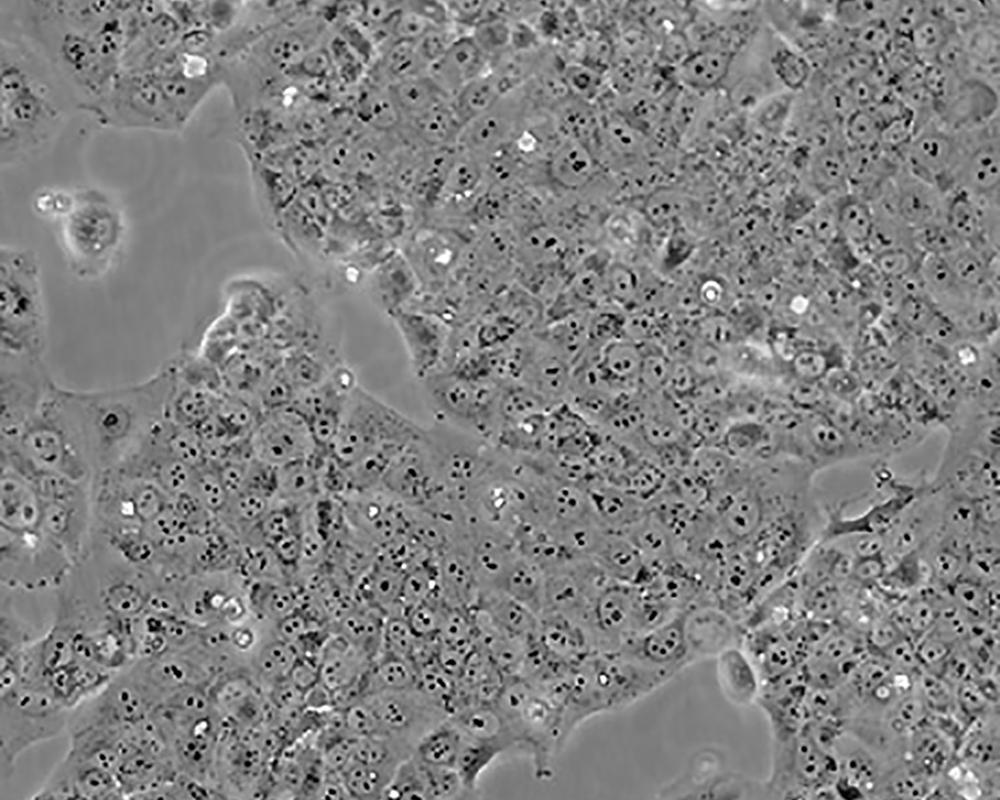

JEG-3

產(chǎn)品名稱 JEG-3

中文名稱 人絨毛膜癌細(xì)胞

組織來源 妊娠性絨毛膜癌;腦轉(zhuǎn)移;女性

生長(zhǎng)特性 adherent

形態(tài)特征 epithelial

細(xì)胞描述 T這是一株超三倍體人類細(xì)胞株